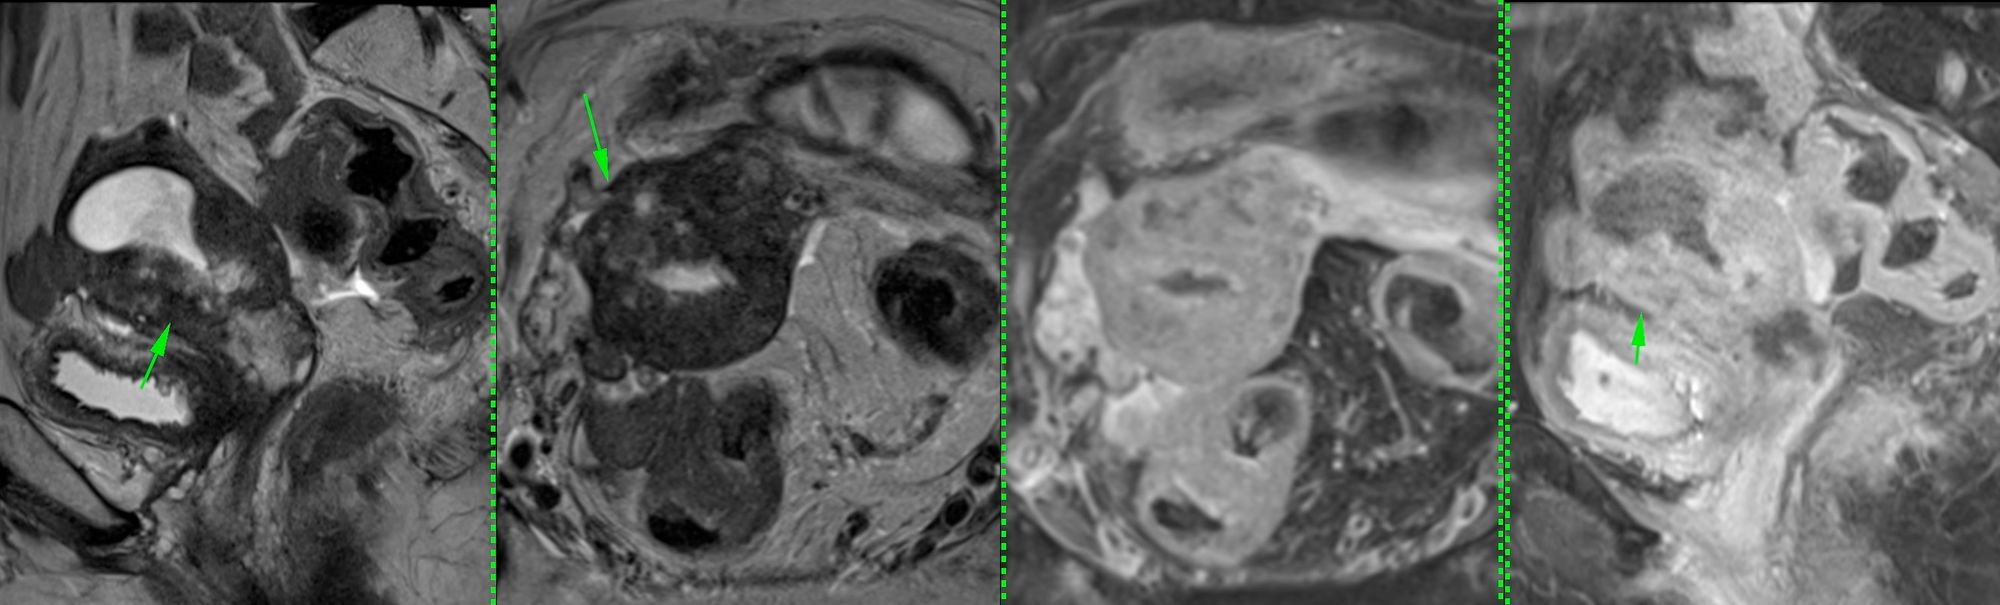

This 68-years old had carcinoma cervix for which she treated. There was recurrence in the uterine cavity, but the lesion could not be targeted easily for a biopsy due to a high-grade lower uterine stenosis and both, USG guided transvaginal and hysteroscopy guided biopsy were deemed not possible and the patient was referred for a CT guided biopsy.

The video below discusses the case, the approach and the way the biopsy was done followed.